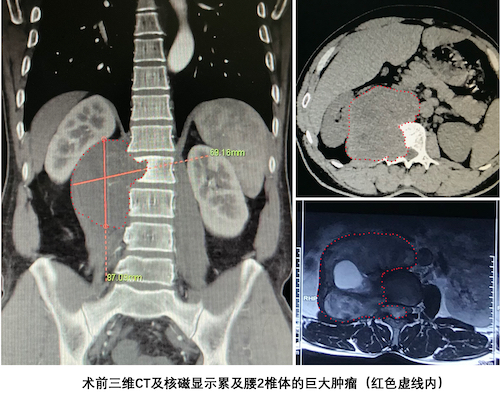

患者李哥(化名)来自湖南永州。李哥和妻子常年在家务农,儿子在上中学,李哥是家里的顶梁柱。然而,一家人幸福宁静的生活在今年初被一纸诊断书打破。一个月前李哥因为腰部不适前往永州市当地医院检查,当地医院CT及核磁共振检查发现,李哥L2椎体层面椎管内和腹膜后有一巨大肿瘤,同时累及了L2椎体和附件。得到检查结果的李哥和妻子为了不影响儿子的学习,并没有告诉他,借口探亲立刻启程前往长沙求医。

李哥入院后的活检结果提示,巨大的占位性病变倾向于神经鞘瘤,这是一种好发于中轻年的良性肿瘤,较大的神经鞘瘤常常与神经根粘连严重。好消息是神经鞘瘤一般有完整的包膜,可通过手术治疗完全切除,从而达到彻底治愈的效果。但是李哥体内的这颗神经鞘瘤瘤体积巨大,侵犯的范围较广,对周围正常结构尤其是腹膜后正常结构干扰极大,肾动脉及腰动脉被极度牵张,右侧肾脏被推顶到肝脏水平,如果肿瘤继续增大,必将危及生命。可以毫不夸张的说,这是一颗深埋在体内的巨大的炸弹,能不能顺利拆下来,事关李哥的生死存亡。

“手术难度很大,巨大的瘤体组织完全切除风险也很高,但我们一起接受挑战,争取给病人一次彻底治愈的机会。”脊柱肿瘤团队成员组织多次会诊,联合麻醉科、放射科、血管外科、泌尿外科等相关科室全面评估患者的病情特点,认为肿瘤病灶目前仅累及L2椎体,但腹膜后的占位病变压迫肾动脉,并可能累及一侧的L2和L3神经根,术中切除瘤体组织时可能导致肾动脉破裂导致难以控制的大出血,牺牲相应节段的神经根可能造成瘫痪。要实现彻底切除肿瘤,就必须同时完整切除L2椎体,并采用个体化定制的3D打印人工椎体重建脊柱的正常序列。